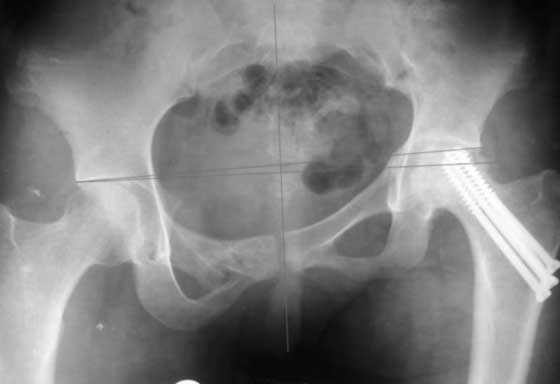

[Ortho] AVN of femoral head and fracture of the pelvis.

До сих пор идут большие дискуссии по поводу высокого центра ротации и единого мнения, насколько я знаю, нет. Компенсация длины, рычагов ягодичных мышц и т.д., а уж при вертикальном смещении таза,влияние его на последующее эндопротезирование просто не узнать (слишком мало наблюдений и много факторов, влияющих на конечный результат). Фото лишний раз подтверждают, укорочение за счет контрактуры.